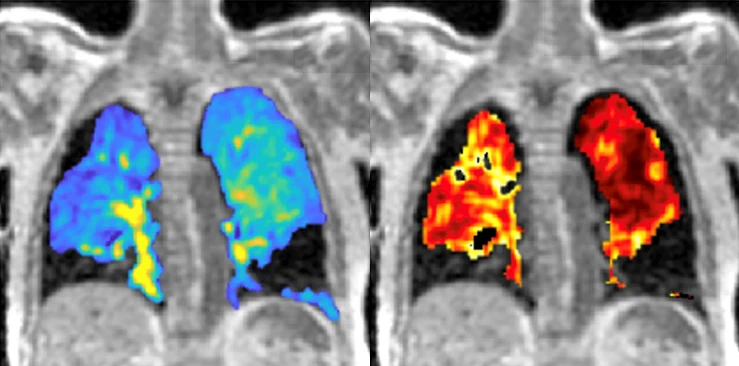

From study design to final reporting, Bioxydyn delivers repeatable MRI biomarkers that reveal tissue function, physiology and change. Our operational excellence and metrology help you compare results across sites, scanners and timepoints.

We're Bioxydyn - delivering quantitative MR biomarkers for pharmaceutical, biotech and academic studies. We combine scientifically leading methods with robust multi-centre study management and transparent analysis, turning complex images into repeatable measurements that support confident decisions.

Disease areas and services supporting quantitative MRI biomarkers across clinical trials.